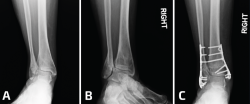

La distracción estable es importante durante el procedimiento de elongación del peroné, dado que permite una colocación más sencilla del material de osteosíntesis. Se han descrito varios métodos para poder fijar el astrágalo a la cara interna de la tibia: se pueden utilizar clavos Steinmann desde el peroné distal hasta el astrágalo, o bien se puede insertar una aguja para fijar al astrágalo contra la cara interna de la tibia, cerrando así el espacio de la gotera medial. Otra alternativa sería la utilización de una pinza de reducción de puntas que se coloca en el extremo distal del maléolo externo y el extremo distal del maléolo interno para restablecer el ángulo intermaleolar. Tras una correcta elongación y rotación, se restablece el espacio claro medial, el paralelismo entre las superficies articulares de la tibia y el astrágalo en la mortaja, y una correcta relación entre ambos maléolos (Figura 5).

Figura 5. En este caso, se observa ensanchamiento de la sindesmosis más consolidaciones viciosas del peroné y el maléolo medial (A). Se debe comenzar por la gotera medial para limpiar todo el tejido cicatrizal remanente. La incisión fue más larga de lo habitual, ya que se planificó una osteotomía del maléolo medial. Tras la reducción y la elongación del peroné, se coloca una pinza de reducción en el eje axial entre la tibia y el peroné (C, D). Al continuar con inestabilidad posterior a la colocación de 2 tornillos (E), se decidió realizar una artrodesis de la sindesmosis